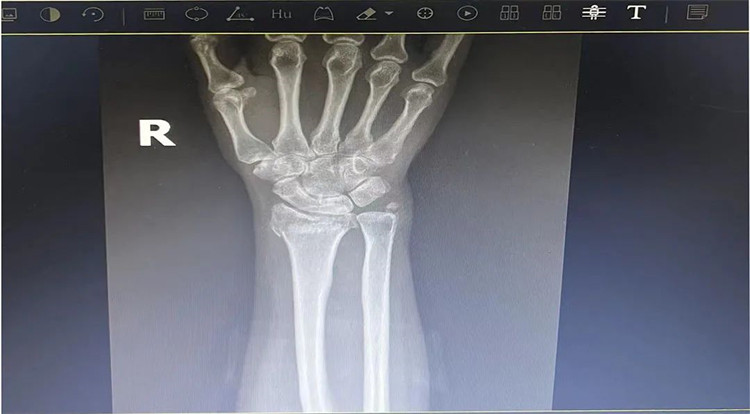

患者老年女性,50多歲,在騎電動(dòng)車停下時(shí)因電動(dòng)車倒下,右手著地,當(dāng)即感覺,右腕及骶尾部腫痛伴右關(guān)節(jié)畸形、活動(dòng)受限,急來我院就診。門診醫(yī)師結(jié)合病史、查體及輔助檢查后,診斷為:右橈尺骨遠(yuǎn)端骨折、骶尾部挫傷并收入住院部。